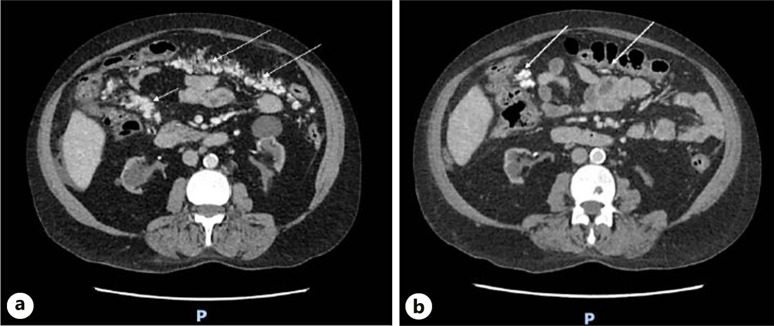

Case presentations: We present 2 cases where the initial clinical picture of calciphylaxis was atypical. The first case is a haemodialysis patient presenting with unilateral acute vision loss, mimicking giant cell arteritis. The second case is a failed transplant graft recipient on peritoneal dialysis with incidental radiological findings of heavily calcified mesenteric nodules.